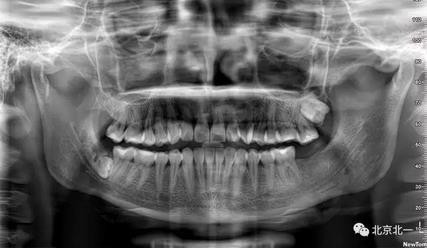

病例資料:一般情況,患者女性,28歲, 主訴:要求拔右側(cè)下頜智齒,檢查:右側(cè)下頜第三磨牙未見萌出, 拍片如圖。

圖一:CBCT顯示右側(cè)下頜水平骨埋伏牙,牙冠距離下牙槽神經(jīng)管接近。

圖二:自帶的CBCT顯示下牙槽神經(jīng)管貼著智齒走形。